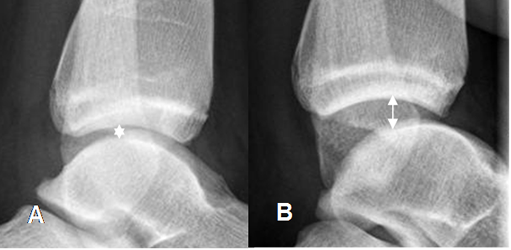

En casos de lesión de la sindesmosis tibioperoneoastragalina, se produce ruptura de los ligamentos interóseos (Tibioperoneo anterior y posterior). En la Rx se observa aumento del espacio entre la tibia y el peroné mayor de 6 mm, en la proyección AP. (12). (Fig 59 A y 59 B). En las Rx de stress puede haber aumento de los espacios articulares, en casos de lesiones ligamentarias completas. (Fig 59 C y 59 D).

Fig 59. Lesión de ligamentos de la mortaja tibioperonea.

A: Rx AP. Aumento del espacio tibioperoneo, por lesión ligamentaria.

B: TAC axial. Aumento del espacio tibioperoneo posterior, por lesión ligamentaria.